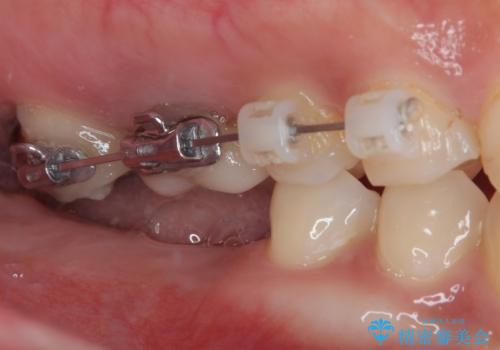

そこで、右上の奥歯に部分的なワイヤーを装着し、さらに矯正用アンカースクリュー(TADs)を併用することで、挺出した歯を圧下(歯を元の高さに戻す動き)させ、下顎にインプラントを埋入するための十分な垂直的スペースを確保しました。

→ この装置は部分的な矯正で、前歯など見える位置にワイヤーがかかることはなく、見た目を気にすることなく、普段通りの生活を送りながら治療を進めることができました。